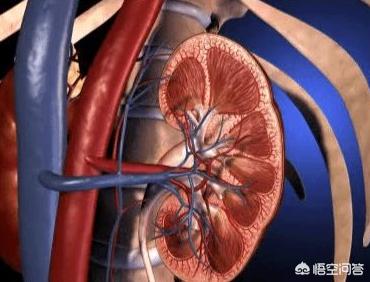

3.腎臓

高血圧が長期間コントロールされないと、腎臓の障害や腎不全を引き起こし、放置すればやがて尿毒症の段階にまで進行する。さらに腎臓の障害が高血圧を悪化させ、悪循環に陥る。

(2)高血圧性腎症:長年にわたってコントロールされていない高血圧が続くと、腎臓に障害が起こり、小腎動脈の硬化が進み、蛋白尿、浮腫、低蛋白などの症状が現れ、重症の場合は重篤な腎症になる。

高血圧は腎機能障害を引き起こす可能性がある

腎臓は常に血液を扱う臓器であり、血液の問題があれば、それが高血圧であろうと高脂血症であろうと、腎臓にダメージを与える可能性がある。したがって、高血圧患者は、特に10年以上高血圧に苦しんでいる人は、血圧をしっかりコントロールしなければなりません。

痛覚過敏につながる腎臓の損傷

腎臓は高血圧に非常に弱い。高血圧は腎臓を長期にわたって損傷し、濾過機能に深刻な影響を及ぼす。極端な条件下では尿毒症を発症することもある。

(3)腎臓:高血圧は糸球体病変を損傷し、軽症の場合は腎機能に影響を及ぼし、重症の場合は短期間で腎不全に至る;

高血圧合併症3:腎臓病

腎臓は私たちの体の排泄器官であり、全身の血液はあらゆる種類の代謝老廃物を腎臓に運ぶが、血管の圧力が高すぎると、血管の壁が厚くなり、内腔が狭くなり、腎臓への血液供給が満たされなくなる。長い目で見れば、腎臓の損傷は容易に起こり、深刻な場合は腎臓の機能低下や腎不全につながることもある。

疫学的知見によれば、高血圧による慢性腎臓病が先進国における尿毒症の主な原因となっている。そして、高血圧による腎症は一度発症すると生涯不可逆的である。